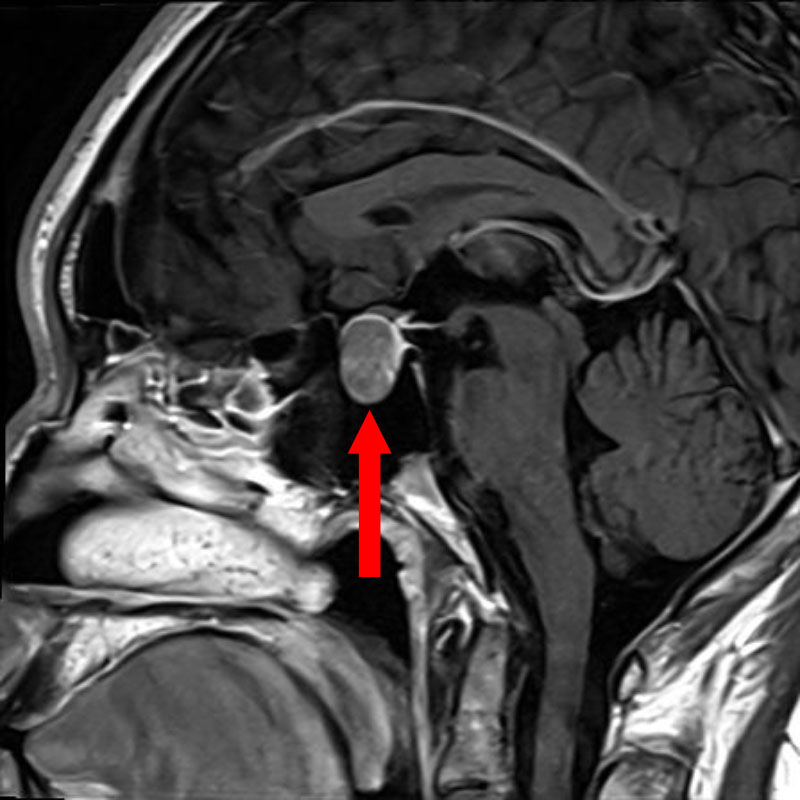

No.’25_78 手術前1

No.’25_78 手術前2